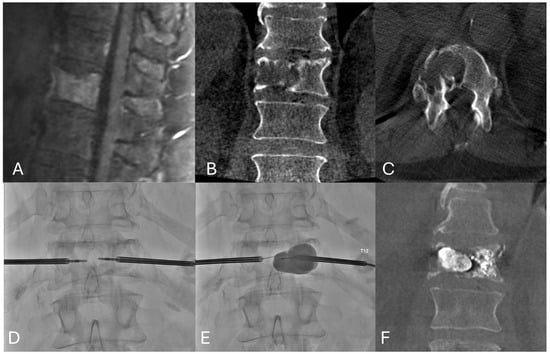

3. Cryoablation

- Masala, S.; Roselli, M.; Manenti, G.; Mammucari, M.; Bartolucci, D.A.; Simonetti, G. Percutaneous Cryoablation and Vertebroplasty: A Case Report. Cardiovasc. Intervent. Radiol. 2008, 31, 669–672. [Google Scholar] [CrossRef][Green Version]